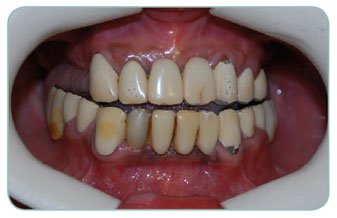

Our patient was using bridge crowns and was not happy of the colour of her teeth. We have replaced all of her teeth with zirconium porcelains and she can smile now in confidence.